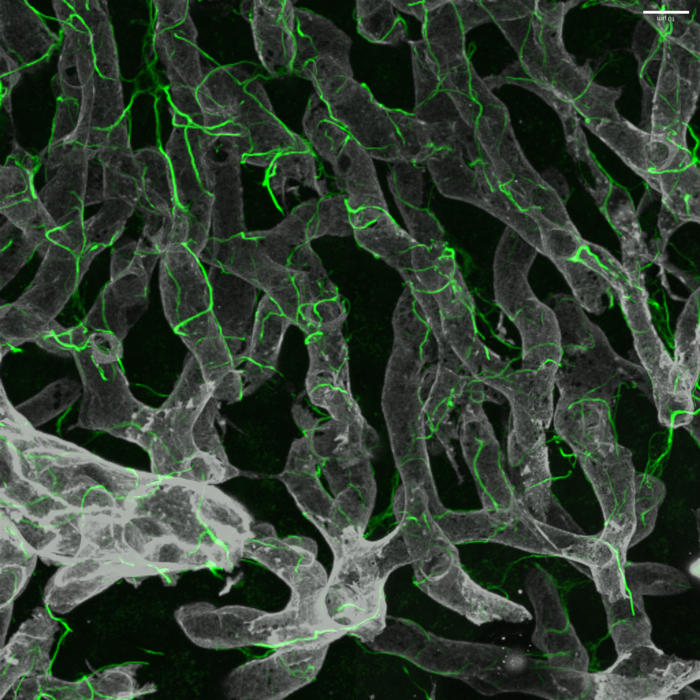

image: Hepatic stellate cells along with their intricate cellular projections (green) are shown wrapped around blood vessels (gray) in the healthy liver. view more

Credit: Wang, et al., Sci. Transl. Med. [volume 15], [add3949] [(2023)]

“We aimed to understand the basis of this fibrotic scarring and identify drug targets that could lead to new treatments for advanced NASH by studying hepatic stellate cells, which are the key scar-producing cells in the liver,” said senior study author Scott L. Friedman, MD, Irene and Dr. Arthur M. Fishberg Professor of Medicine, Dean for Therapeutic Discovery, and Chief of Liver Diseases at Icahn Mount Sinai. “In combining this new glass liver imaging approach—an advanced tissue clearing method that enables deep insight—along with gene expression analysis in individual stellate cells, we have unveiled an entirely new understanding of how these cells generate scarring as NASH advances to late stages.”